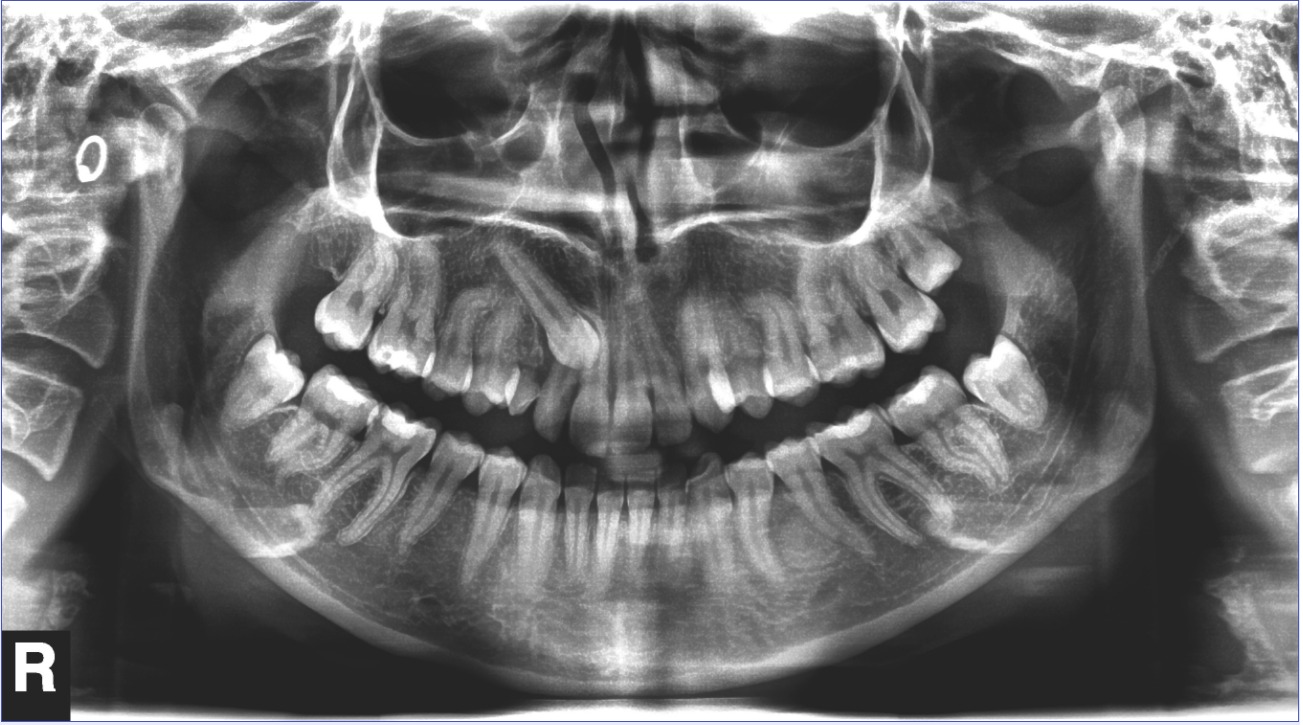

Paciente de 28 años que acude a la consulta con el fin de mejorar su sonrisa. Presenta Clase II molar y canina, sobremordida 2/3, compresión maxilar, mordida cruzada posterior derecha, canino superior derecho impactado.

panorámica inicial